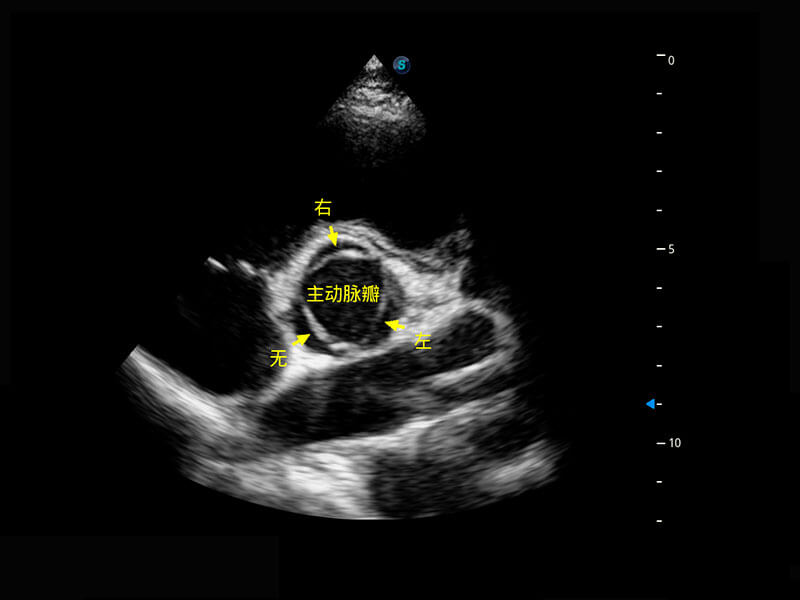

胎心筛查

P60搭载一系列胎儿心脏成像技术,实现精细的胎儿心脏评估。

• 四腔切面

• 四腔心血流

• 右室双出口

• 胎心容积成像